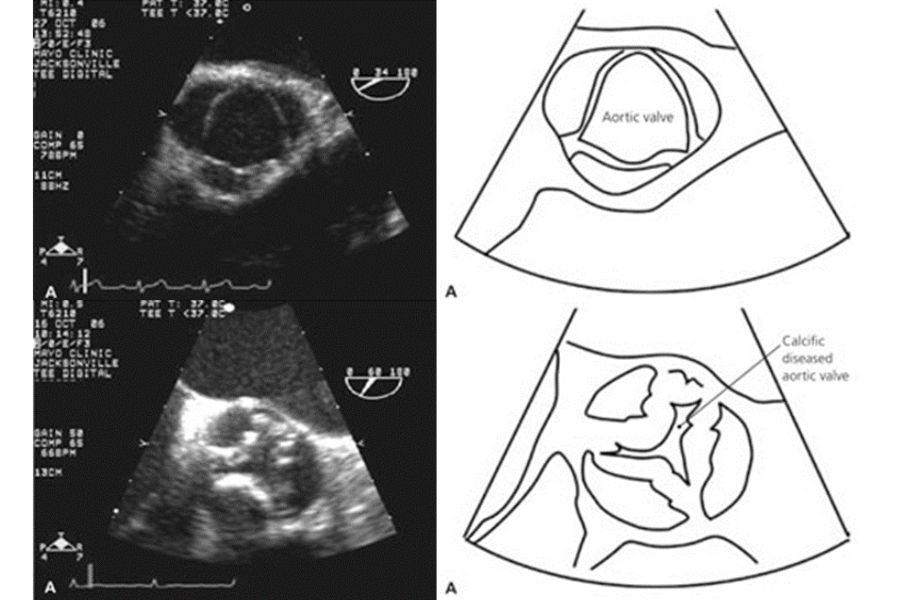

Unlike the mitral valve, which serves as the heart’s entry point (as illustrated in Figure 1), the aortic valve serves as the exit, regulating blood flow from the main heart pumping chamber, the left ventricle. A comprehensive assessment, including a physical examination by a doctor, and advanced diagnostic investigation, such as the use of ultrasound evaluation by echocardiogram (as shown in Figure 2), is crucial for determining if the afflicted valve is diseased, and for gauging the extent and severity of the valve dysfunction.

Figure 2

The most common cause of AS stems from the natural wear and tear of the aortic valve, particularly in the elderly (as illustrated in Figure 3c). In less frequent instances, AS may result from previous infections affecting the aortic valve, such as in rheumatic heart disease (Figure 3d), or from congenital abnormalities where individuals are born with deformed aortic valves, known as bicuspid aortic valves (Figure 3b). Unfortunately, there is currently no proven treatment which prevents or delays the progression of AS.

Figure 3: Aortic Stenosis Causes